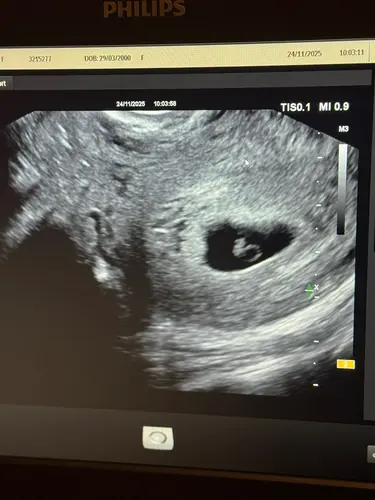

Als je vorige week maandag uitkwam op 6.3 en nu op 7.1 is dat prima. De eerste weken kan elke millimeter al een verschil van een paar dagen aangeven. Het is nog zó klein dat er met 3x meten door dezelfde persoon op hetzelfde moment zelfs 3 verschillende termijnen op het scherm kunnen komen te staan. De zwangerschapsduur wordt niet voor niks pas definitief bepaald bij de termijnecho (tussen de 10-12 weken).